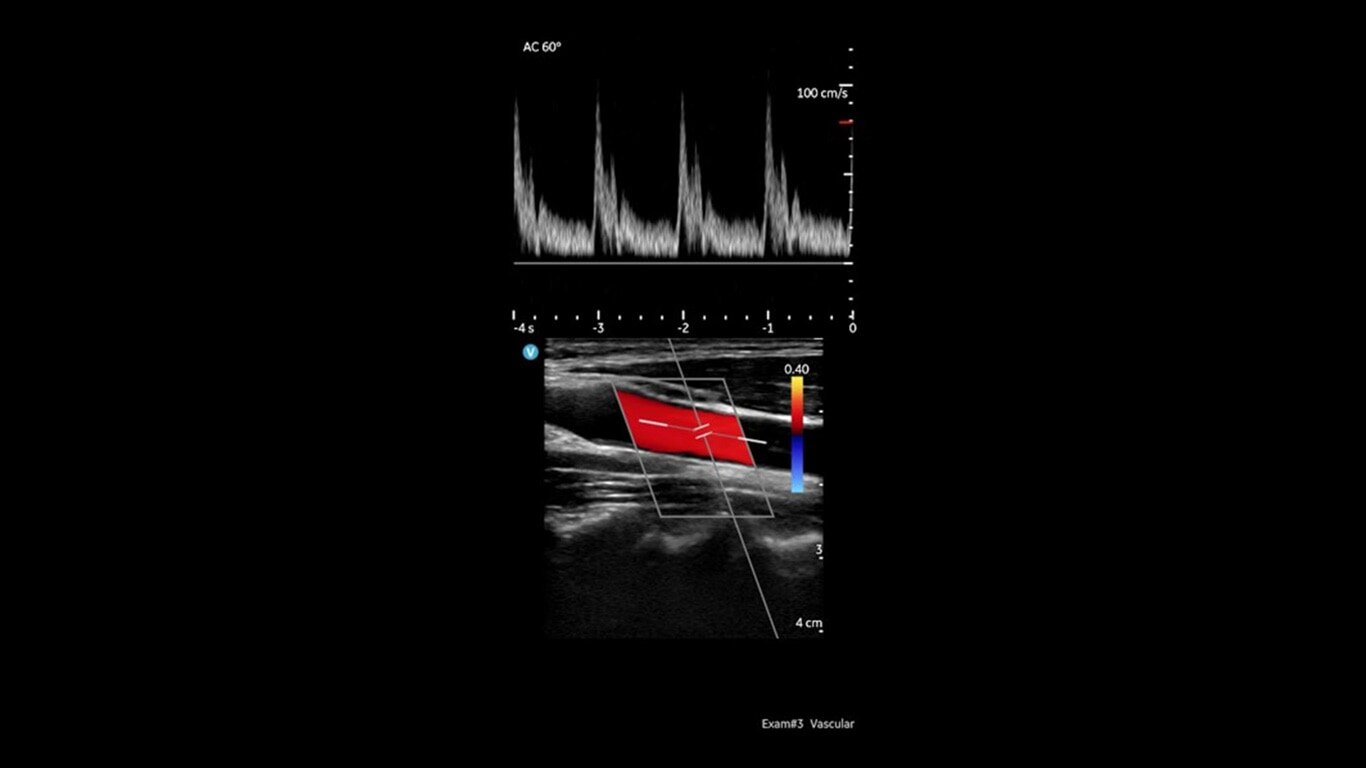

Don’t miss a beat between cardiac, vascular, and other evaluations

Vscan Air SL handheld ultrasound offers wireless freedom and maximum portability with two transducers in a single device. Delivers crystal-clear images at the point of care. Sector-phased array transducer is ideal for rapid cardiac assessments. The linear array transducer allows you to move from a cardiac to a vascular assessment without missing a beat.

Built for both new and experienced handheld ultrasound users with basic and advanced assessments in mind. Now including: B-mode; Color Doppler; PW Doppler; M-mode.